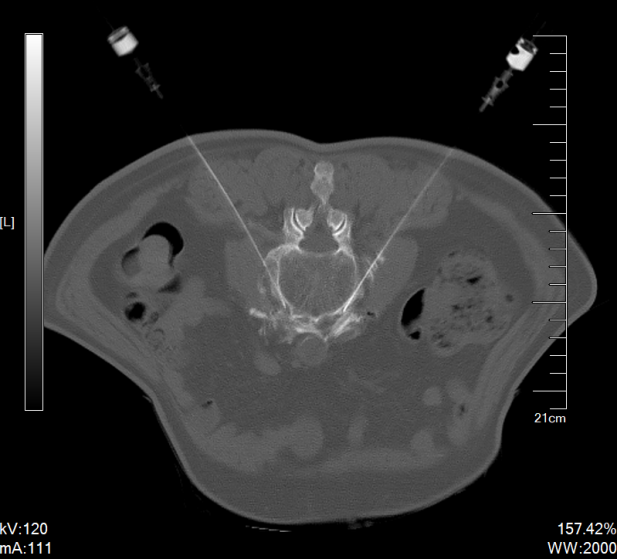

疼痛科团队术前认真讨论,并跟家属充分沟通手术风险,最后确定手术方案。在CT影像的帮助下,疼痛科医师们顺利为患者实施CT引导下腰交感神经射频消融+无水乙醇毁损术。手术后患者便感觉双下肢疼痛和麻木症状减轻,体温监测示其双侧足背皮温升高1.5℃-2.0℃。次日上午患者感觉双下肢疼痛和麻木症状显著减轻,夜间睡眠质量大幅改善,对治疗效果感到满意。

目前,疼痛科开展有两种微创介入手术方法治疗干预糖尿病性周围神经痛。一种方法是腰交感神经节射频消融+无水乙醇毁损术,通过CT影像精准定位L2椎体下缘、L2-3椎间盘和L3椎体上缘,对腰交感神经节实施热凝和化学双重毁损,阻断交感神经对下肢血管收缩异常指令,从而扩张血管以改善组织血供,以缓解疼痛和麻木症状。另一种方法是脊髓电刺激器植入术(SCS),通过植入式电极向脊髓特定节段输送低强度电脉冲,从而阻断或调制疼痛信号传导,有效缓解疼痛。